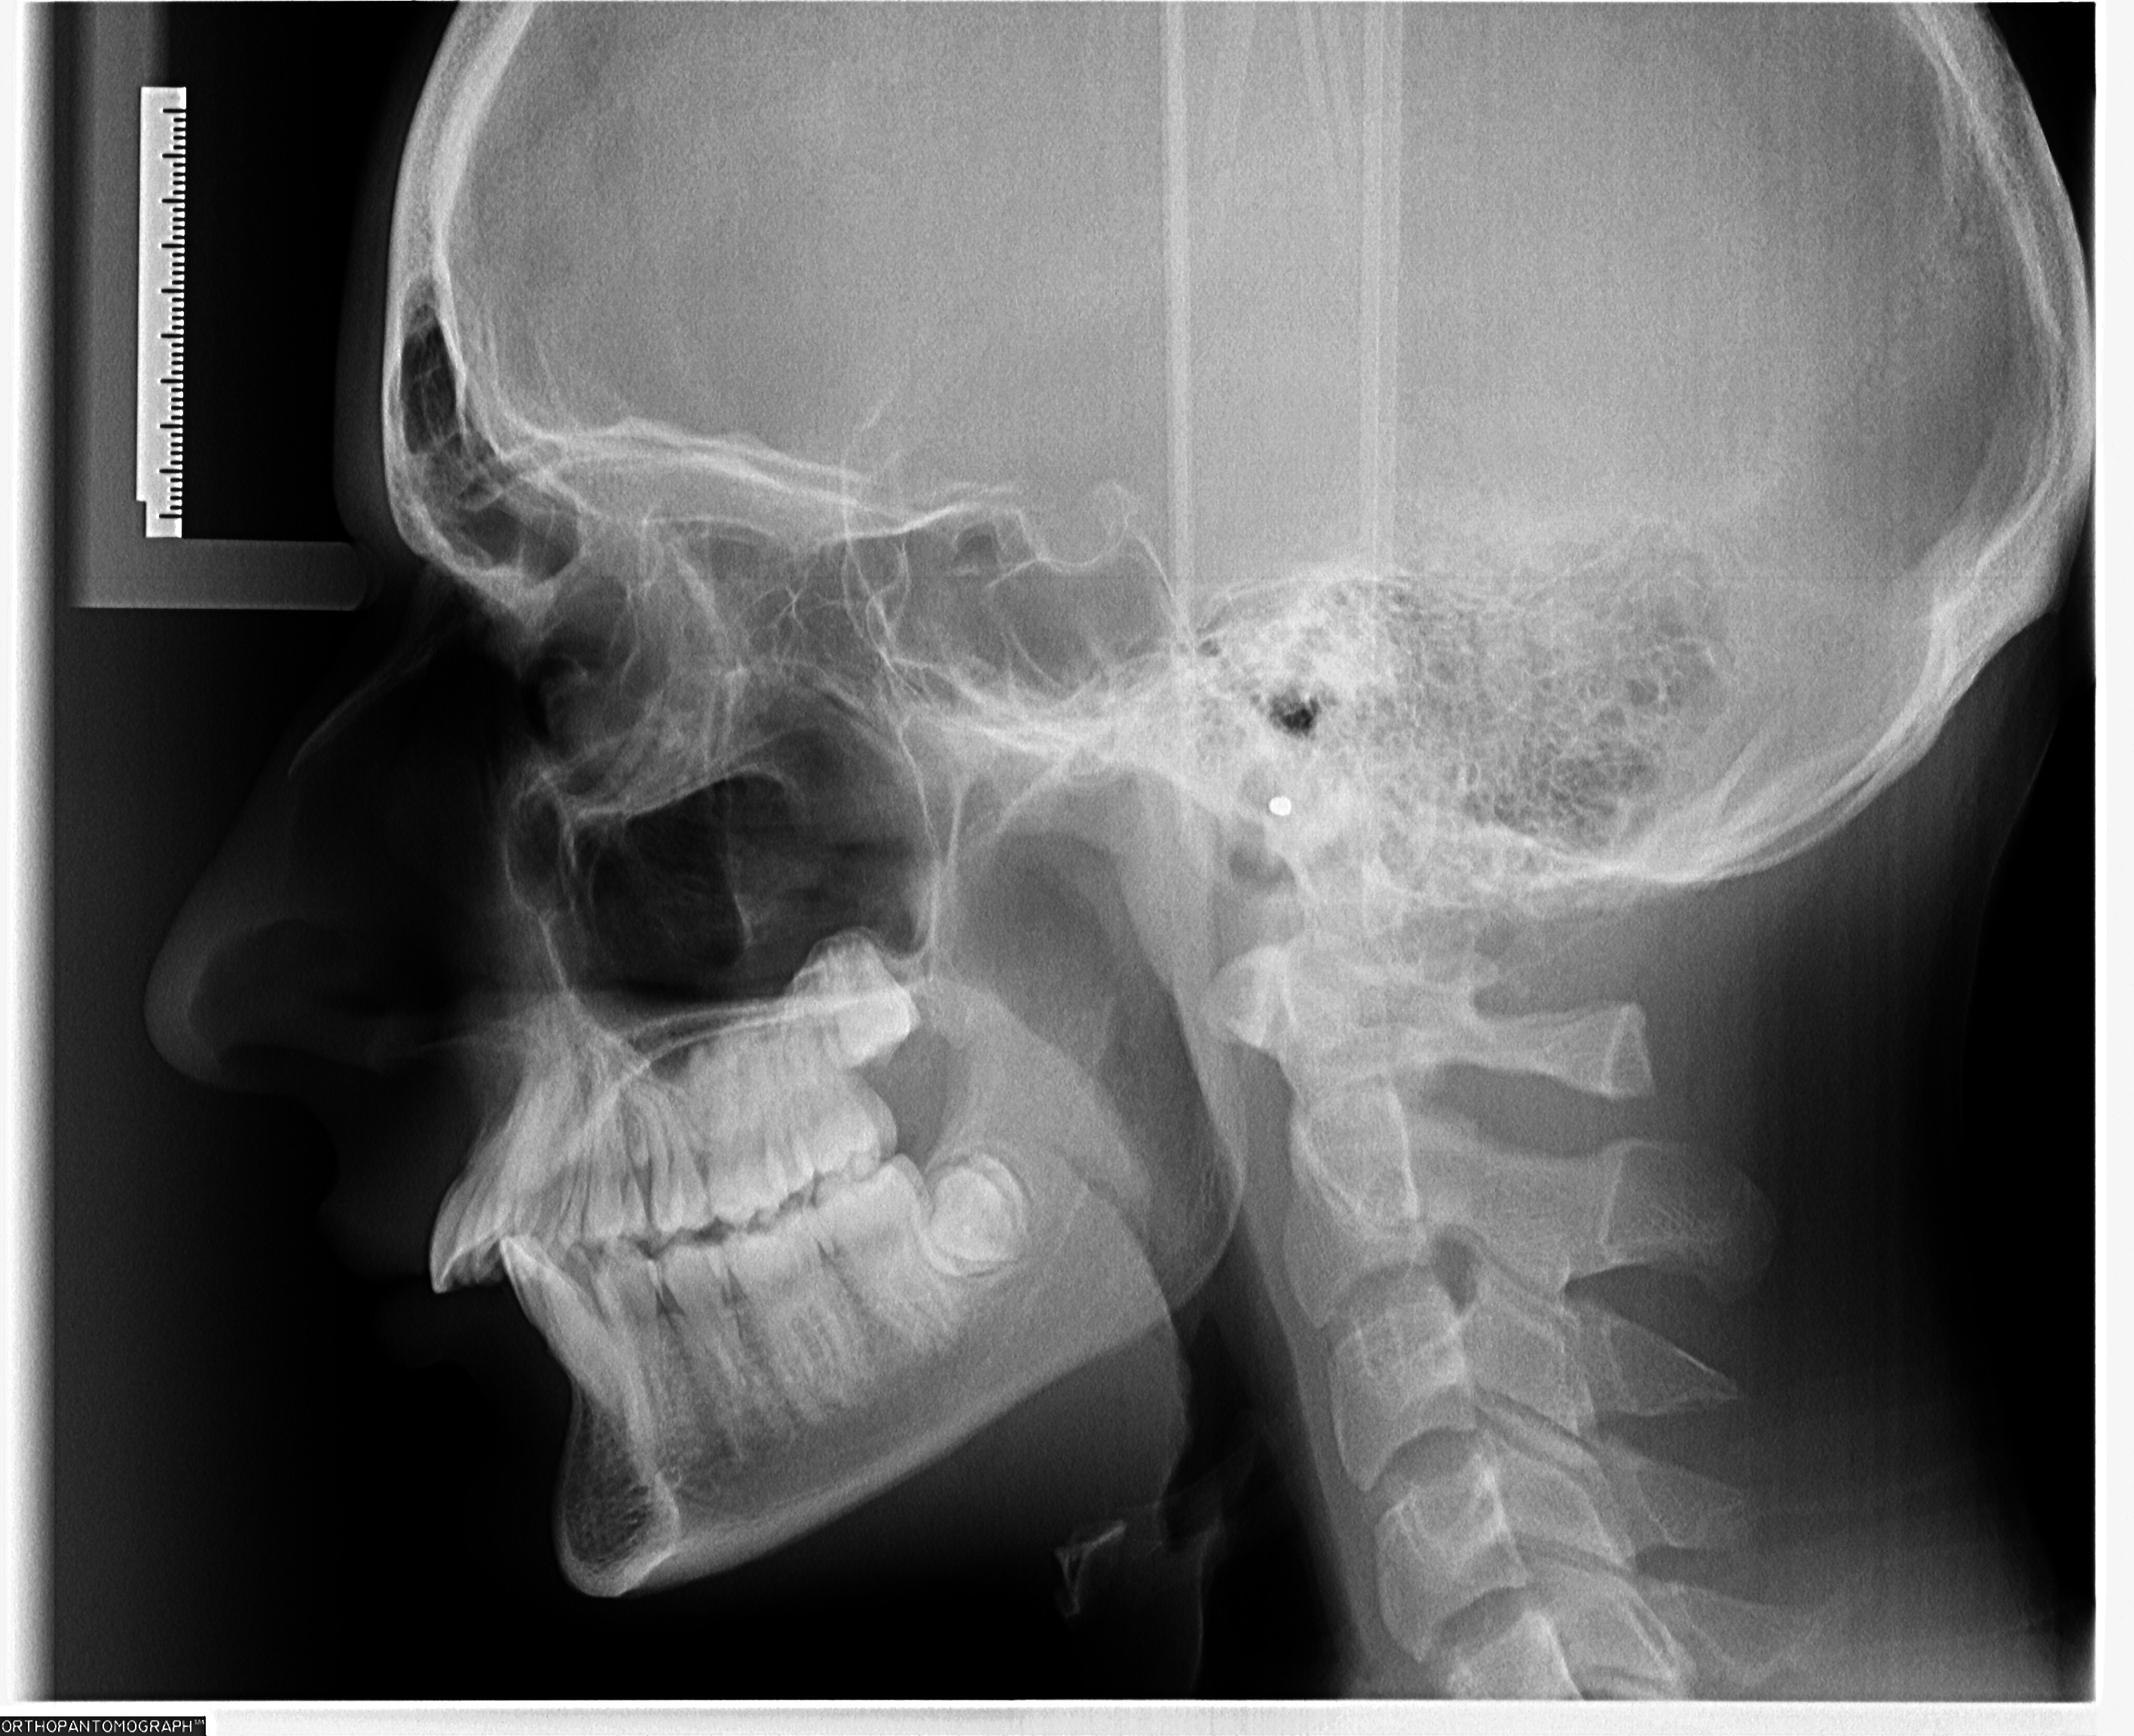

Havent posted here for a while. After talking with a private ortho he told my dentist to give me a referral to a maxilofacial surgeon.

Cannot wait for this, he said he thinks i have a high chance of having a bimax covered due to a misaligned and a deep bite.

IMG 0419